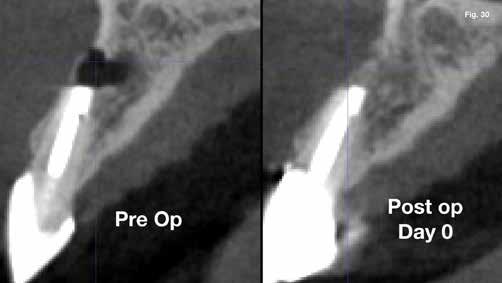

Anyagok és módszerek: 42 éves nő fordult a szerző rendelőjébe tüneti apikális parodontitisszel. A PA röntgenfelvételen az apex körül sugárzástól átlátszó kép és extrudált gyökércsatorna obturációs anyag volt látható, a CBCT-n megőrzött vestibuláris csont mellett (1–2. ábra). Mivel az elmúlt három évben kétszer

végeztek NSRCT-t, és a gyökércsatorna obturáció homogénnek, de túlságosan extrudáltnak tűnt, sebészi kezelés mellett döntöttek.

Eredmények: (3) és RAC-B összpontszám 2 (2-2-2/ 2) az 1 éves CBCT-követéskor (30–32. ábra), (4, 5,). Az 1 éves követéskor a lágyrészeken nem volt látható recesszió, csak enyhe színkülönbség a sebgyógyulás és a keratinizált szövet között, de ez a páciens számára nem aggályos (28. ábra).